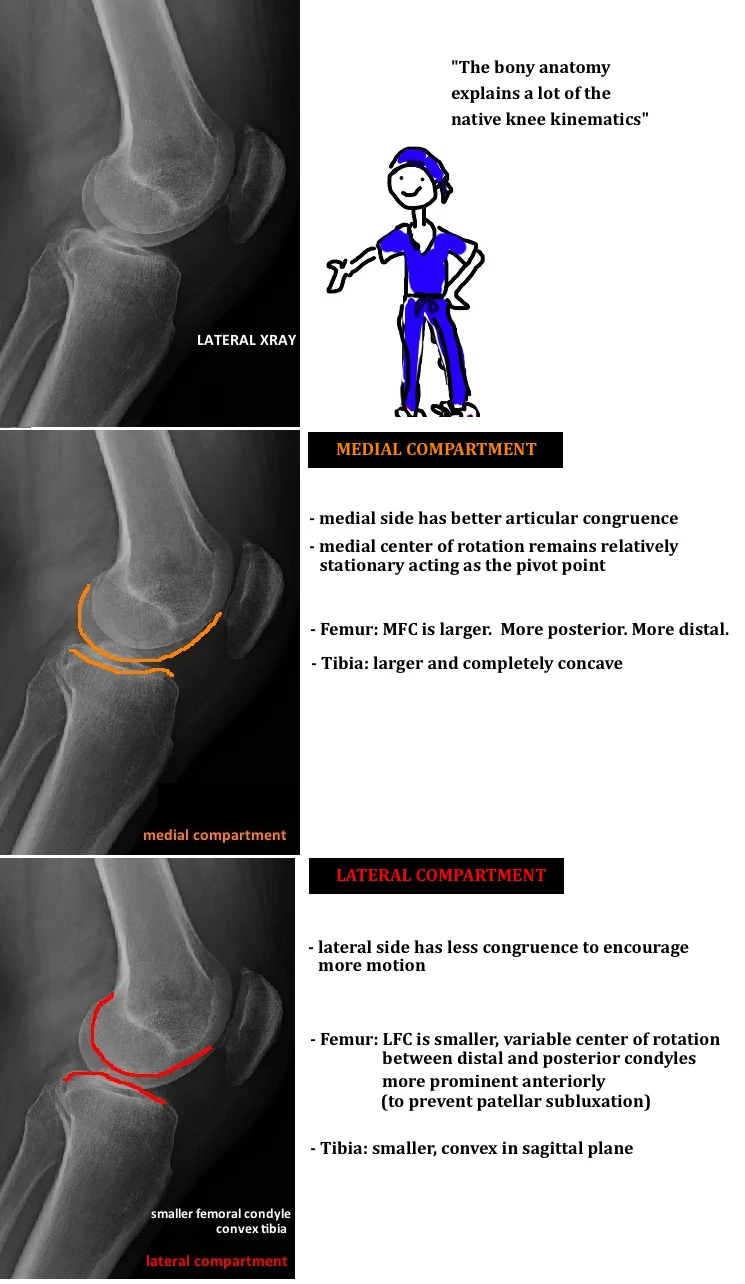

Native Knee Kinematics Hip Knee Book